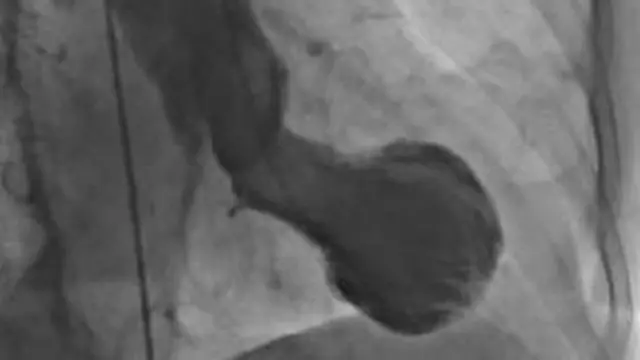

اسے 'تاکوٹسوبو سنڈروم' بھی کہا جاتا ہے جو انسان کے ٹوٹے ہوئے دل سے اسی نام کے جاپانی برتن سے مشابہ ہے۔ شکستہ دل سنڈروم صدمے کے سبب ہوتا ہے۔

،تصویر کا ذریعہCHRISTIAN TEMPLIN, UNIVERSITY HOSPITAL ZURICH